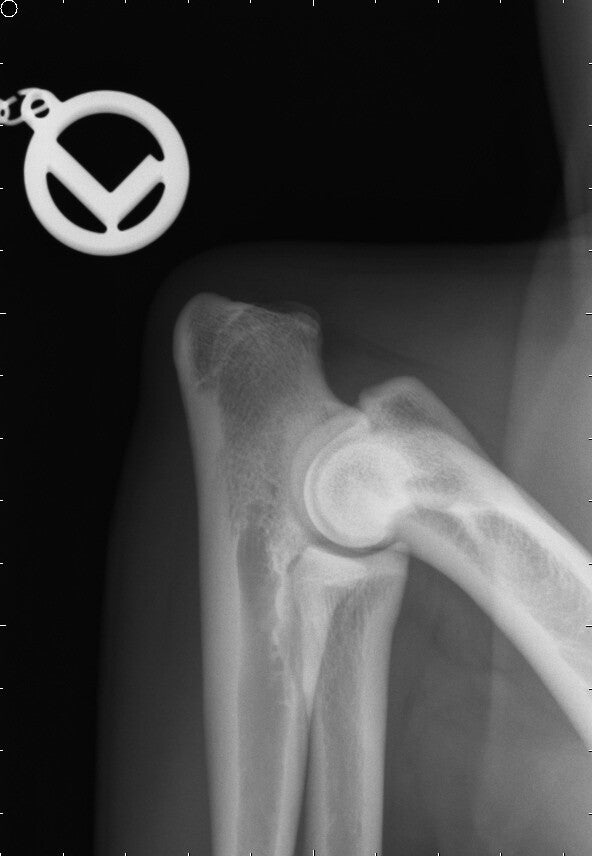

ED-, OCD-, LÜW-& Spondylosegutachten

Bewertung von Ellbogengelenken (ED) nach IEWG, Schultern (OCD) und Wirbelsäulen (Spondylose) für rassespezifische Anforderungen.